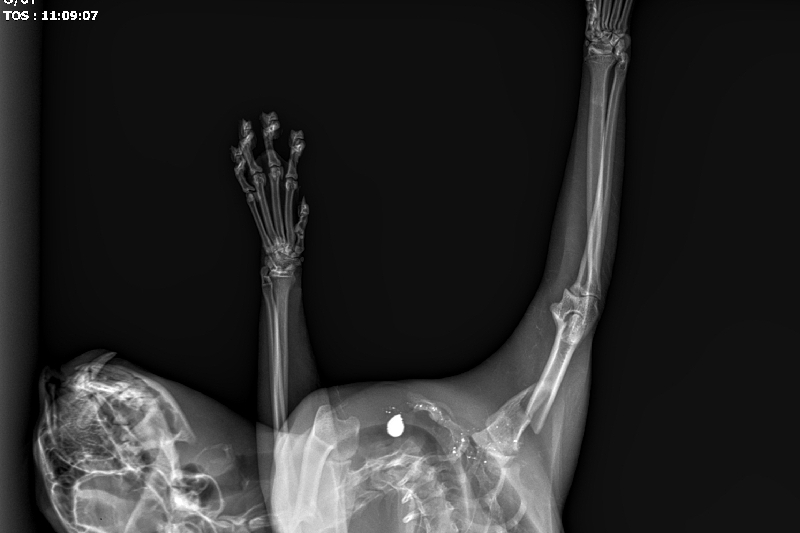

The bullet broke his arm and is currently lodged inside his body with many fragments scattered throughout his shoulder. I could go on about the vile nature of his attacker, but this isn't about him/her. It's about Jonesy.

From his initial consultation, it appears as if Jonesy might need two separate procedures. The first is to get the bullet and the fragments out of his body. The second is to either repair his leg or amputated it all together.

In this post I will add pictures of him and his x-rays. All funds received will be used for his medical procedure(s) and post Op care/visits.